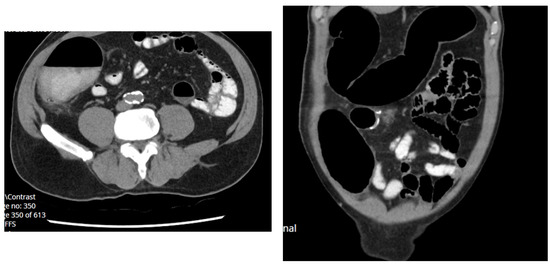

2.1.1. Case 1

2.1.2. Case 2